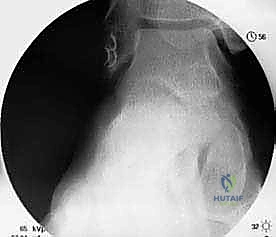

2. التقييم بالمنظار (Arthroscopy) بتقنية 4K:

قبل البدء في إعادة البناء، يقوم الدكتور هطيف بإدخال كاميرا دقيقة جداً (منظار) داخل مفصل الكاحل. تتيح شاشات الـ 4K رؤية تفاصيل المفصل بوضوح مذهل. يتم في هذه الخطوة تنظيف المفصل من أي أنسجة ملتهبة، إزالة الشظايا العظمية أو الغضروفية السائبة، ومعالجة أي تلف في الغضروف ناتج عن عدم الاستقرار المزمن.

4. حفر الأنفاق العظمية:

باستخدام أدوات جراحية دقيقة، يقوم الدكتور هطيف بعمل أنفاق صغيرة جداً في عظم الشظية (Fibula) وعظم الكاحل (Talus) وعظم العقب (Calcaneus). تعتمد هذه الخطوة على المعرفة التشريحية العميقة لضمان وضع الأربطة الجديدة في مسارها التشريحي الطبيعي (Anatomical Reconstruction).